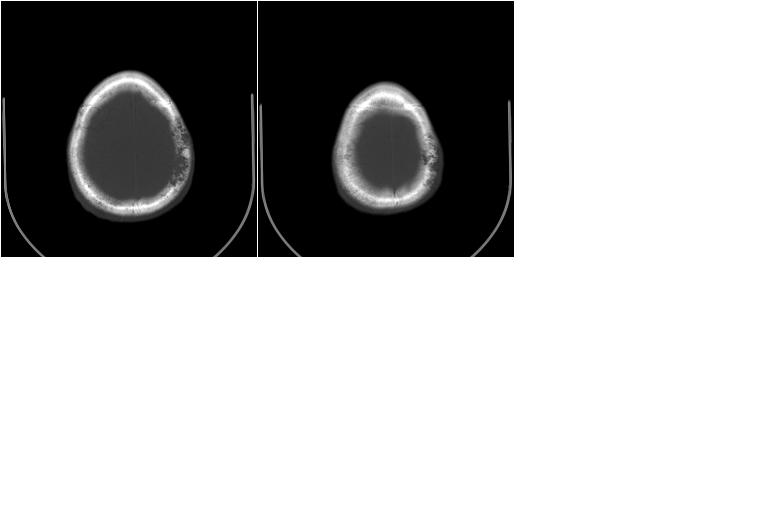

以下是引用边生丽在2009-8-17 11:43:00的发言:[br][br] [br] 右肺中心型癌伴右肺下叶不张、双肺转移并癌性淋巴管炎、心包和双侧胸腔积淮(转移?)、脑转移、肝转移、多骨(颅骨、椎骨)转移。 [br] [br]

以下是引用随光逐影在2009-8-17 14:09:00的发言:[br]支持 右肺中央型癌伴右肺下叶肺不张,纵隔淋巴结转移,双肺转移并癌性淋巴管炎,心包和双侧胸腔积液,脑转移、肝转移、多发性骨(颅骨、脊椎)转移。